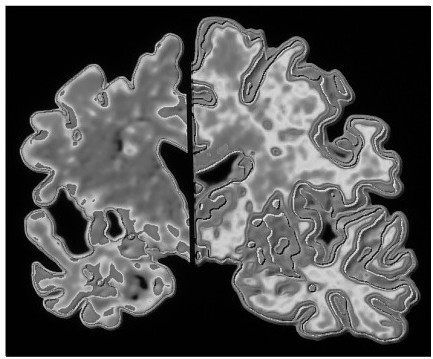

左侧是阿尔茨海默氏病患者的脑切片,右侧是没这种病的人的脑切片。左侧有脑萎缩,这是神经细胞的死亡造成的。